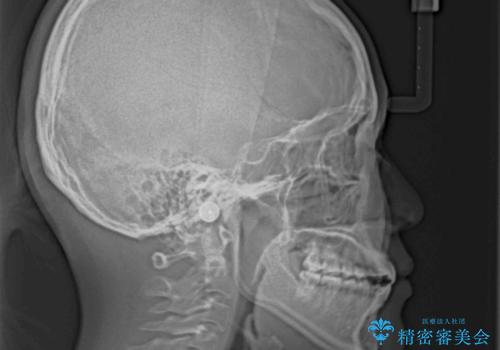

【モニター】隙間だらけの前歯を治したい インビザラインによる矯正治療

- 上下前歯の隙間と咬み合わない前歯を気にして来院された患者様です。

開咬の治療は、前歯を閉じるように動かすとともに、上下臼歯を圧下(骨内にめり込ませる)させることで進めて行きます。

インビザラインは臼歯の圧下を効果的に行えるため、インビザラインを用いて矯正治療を行うこととしました。

開咬とすきっ歯は、舌の突出癖改善が必須となるため、トレーニングを徹底的に行うよう指示しました。

仕上がりとしては、もう少し上下前歯を接触させたかったのですが、ここまで改善されたことで患者様は大変満足され、治療を終えることとなりました。